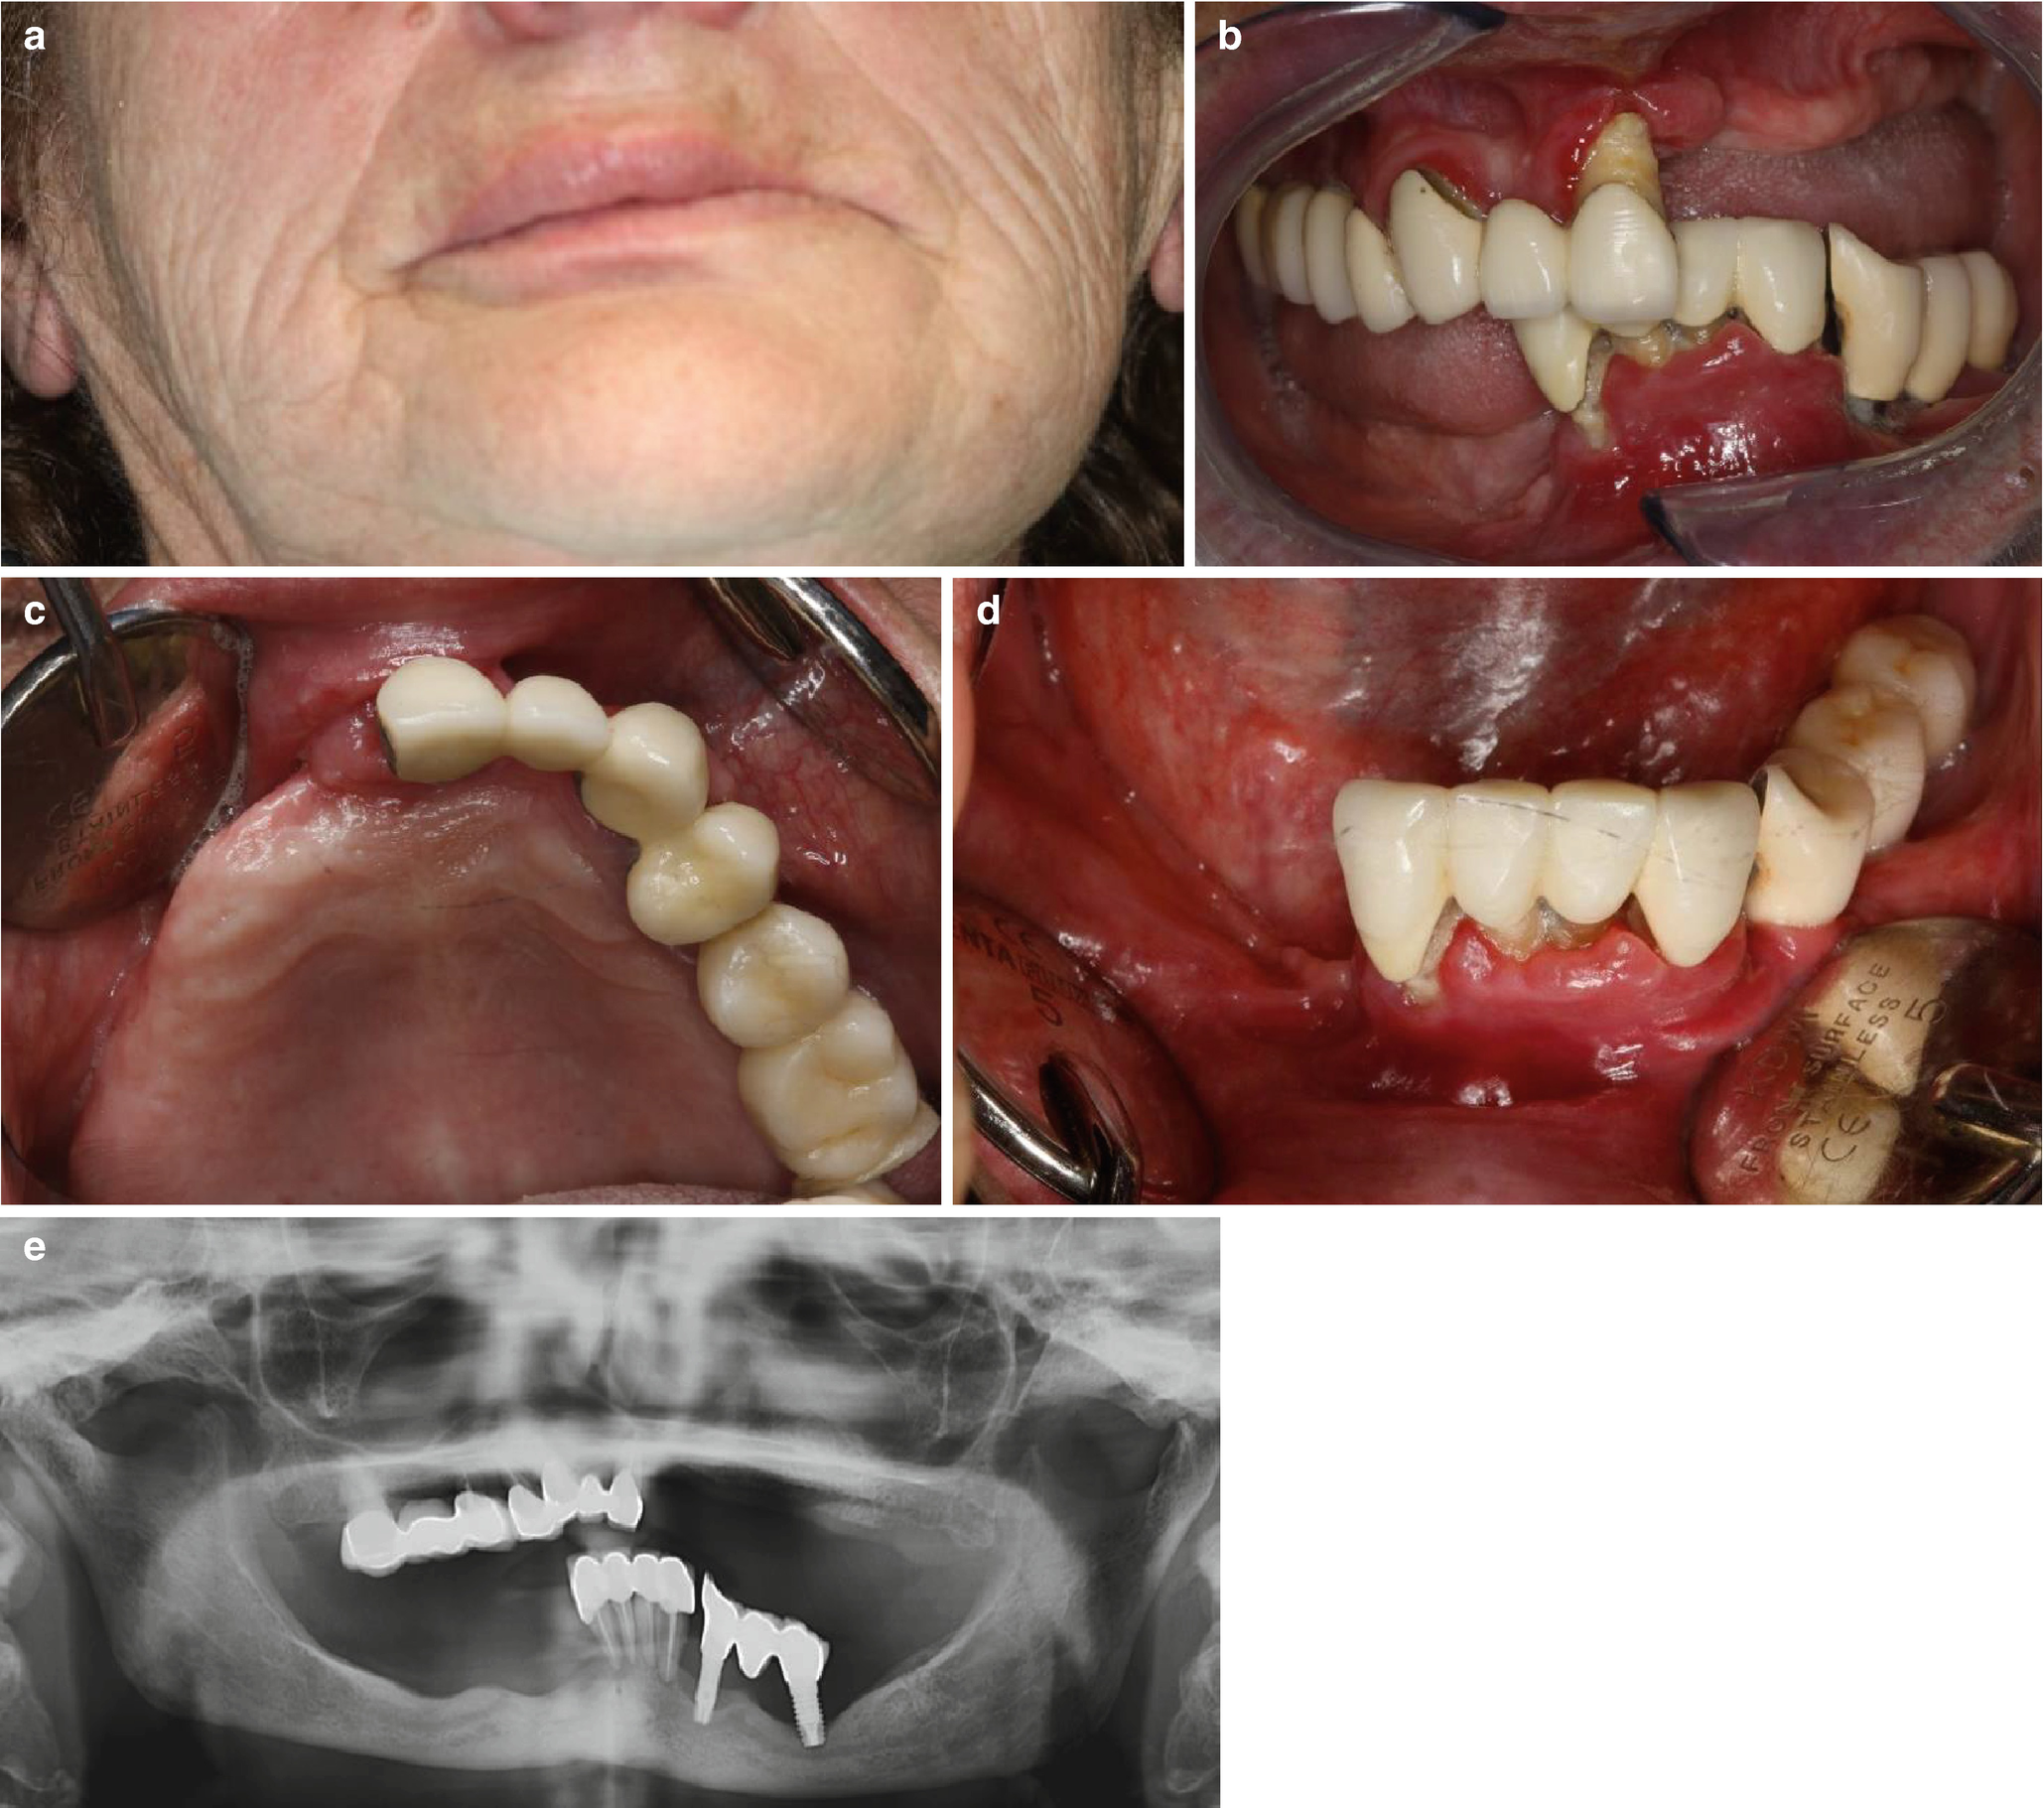

A 62 old year old female patient had one Reclast treatment zolendronic acid. Other health conditions are arthritis diabetes and asthma. The authors discuss the current evidence regarding the risks of dental procedures in patients receiving IV bisphosphonates for this indication. The study was divided randomly into two. Thats when I got the information about doing dental work prior to infusion.

Dental strategies for osteoporosis drugs. Is a rare side effect however it is important that you know about it and take steps to protect your dental health. Other health conditions are arthritis diabetes and asthma. A recent two-day whirlwind trip to New York City left my head spinning as I sought to comprehend the complex world of prescribing behavior by physicians who write prescriptions for. A localized clinical approach eg treating a sextant at a time to dentoalveolar surgery in.

The authors discuss the current evidence regarding the risks of dental procedures in patients receiving IV bisphosphonates for this indication. Zoledronic Acid Zometa Reclast Author. They also evaluate important risk factors and the decision-making pathway in such cases. Last week while eating soft food fish and bread I broke the molar in half. HI thereI was actually waiting for the other shoe to drop and it kind of did.

On the basis of existing. In the case of antiresorptive agentsmedicines that help strengthen bonesthese medications have been associated with a rare but serious condition called osteonecrosis OSS-tee-oh-ne-KRO-sis of the jaw ONJ that. Kantenlose Komposit-Füllkörper mit sphärischen Füllstoffen. Reclast is only part of a complete program of treatment that may also include diet changes and taking calcium and vitamin supplements. A localized clinical approach eg treating a sextant at a time to dentoalveolar surgery in. If you need to have any dental work especially surgery tell the dentist ahead of time that you are using Reclast.

I am 73 years old and do have Osteoporois. Zoledronic Acid Zometa Reclast Print PDF. HI thereI was actually waiting for the other shoe to drop and it kind of did. In the case of antiresorptive agentsmedicines that help strengthen bonesthese medications have been associated with a rare but serious condition called osteonecrosis OSS-tee-oh-ne-KRO-sis of the jaw ONJ that. Dental fistula is found among people who take Reclast especially for people who are female 60 old have been taking the drug for 2 - 5 years. The phase IV clinical study analyzes which people take Reclast and have Dental fistula.